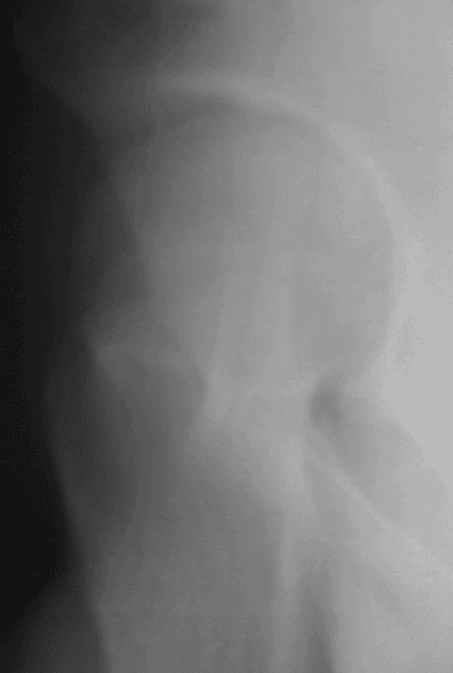

Уважаемые коллеги! Заканчивая обследование больного с переломо-вывихом бедра сделал ему обычные R-томограммы. Кажется удалось "поймать" и отломок и донорское место. Мои выводы - в скиаграмме. Считаю, что это передне-нижний фрагмент головки, образовавшийся вследствии отрывного перелома. На томограммах отломок обозначаю длинной стрелкой, а место откуда он оторвался - более короткой. Учитывая тот факт, что его размеры по КТ 25 х 15 мм считаю, что его фиксация на место необходима для профилактики артроза, что при 16-ти летнем возрасте пациента важно в плане максимального отодвигания эндопротезирования. Планирую оперировать его 24.05.05 г. Результаты представлю.

Прямой при поступлении